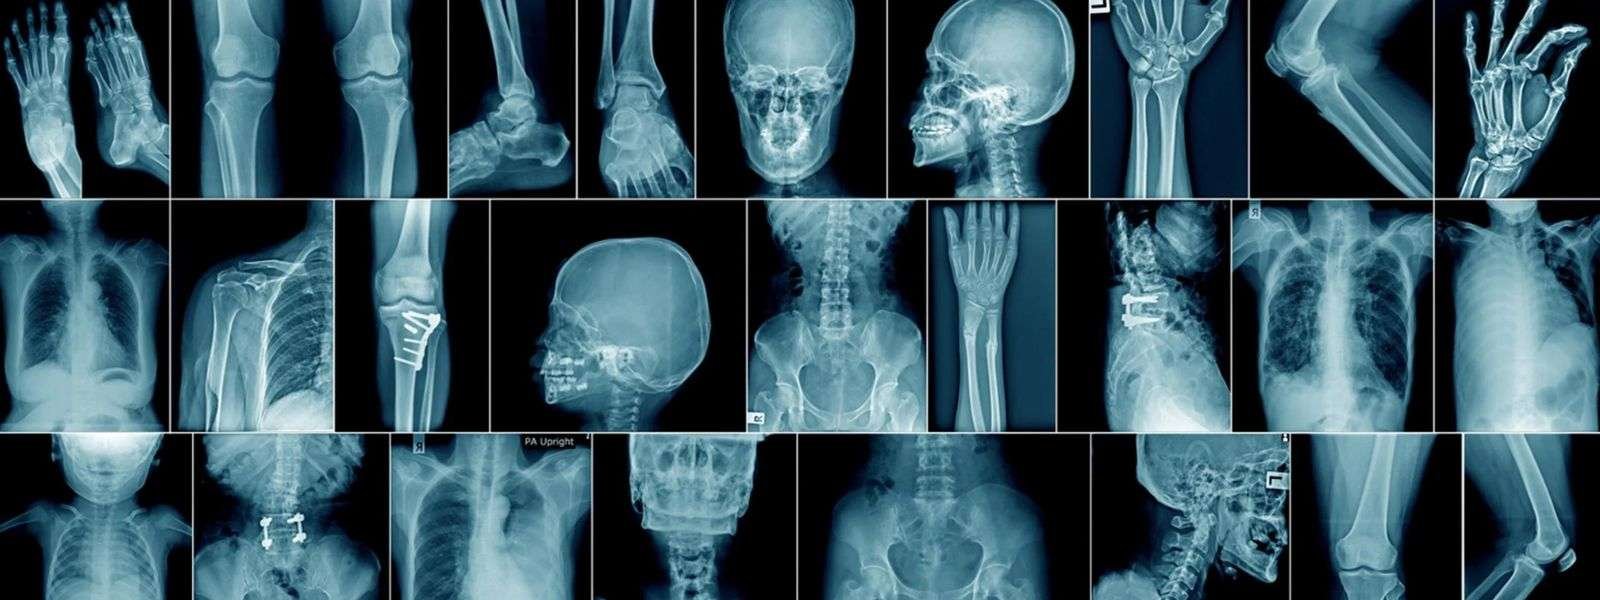

X-ray and CT scans activities at government hospitals are at risk due to the shortage of radiologists.

Government Radiological Technologists Association Chairman Chanaka Dharmawickrama told News 1st that the country is in need of 400 radiologists.

He noted that even if the x-ray and CT scan devices are repaired, there is no staff to operate those devices.